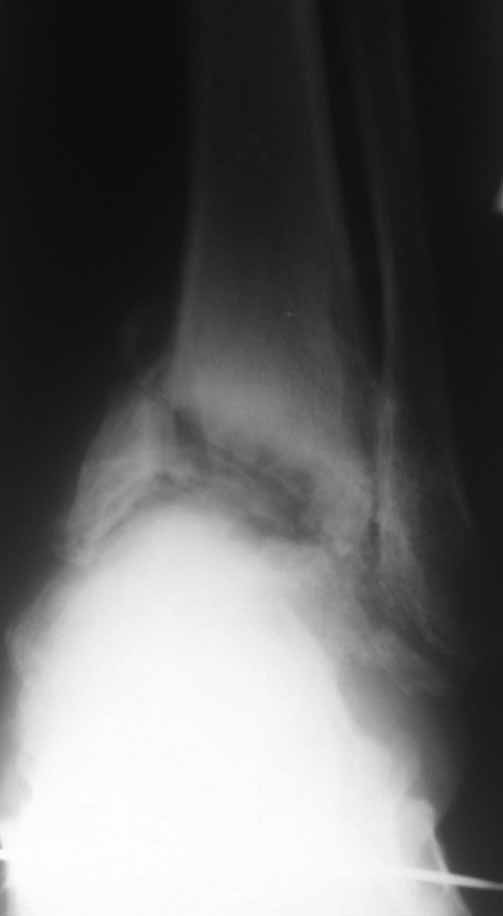

Опять прошу прощения за качество фото, но принципиальные моменты мне кажется, что видны.

Из того, что я вместе с лучевыми диагностами разглядел - нельзя исключить остеомиелит (?) - есть краевая реакция, куча элементов, похожих на секвестры. Смущает полное отсутствие местной и системной реакции - к анализам не придраться.

Наверное здесь имеется асептический некроз таранной кости с патологическим внутренним подвывихом стопы на фоне подагрической артропатии.

Склоняемся к мысли, что все таки Charcot's Joint.

На КТ срезах вместо тарана некротический остаток, который явно не пригодится как пластический материал. Вместе него блок из алло-кости

(консервированная головка бедра), или лучший вариант с удалением тарана с последующим артродезированием. Тибиа к пятке и канюлированные винты, для уверенности добавленный аппарат Илизарова усилит конструкцию.